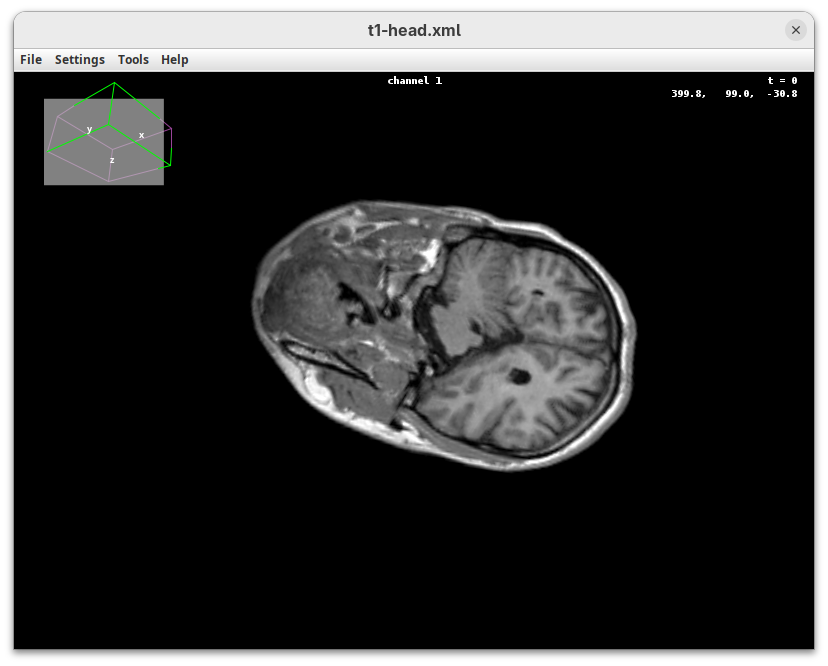

Transformation

The transformation menu has controls for rotating, translating, and scaling the sample. We can either add values or manually interact with the 3D Animation window to reorient the sample. Let’s try the latter.

- Left-click on the head and move it around.

That’s a great way to see your sample from different angles. And note that the values in the Transformation panel get updated every time you move the sample interactively. In this way you can roughly position the sample and then check and update the precise values for the target transformation.

- Press

Resetand change theRotation Yto180to look at the right side of the head.

- Now change

Scaleto5andTranslation Xto-500to focus on the nose.

Resetto return the sample to its original position.

Cropping

Another useful 3Dscript option is the ability to crop the bounding box to show the inside of the sample. We can do it in the XYZ directions or in the near/far axis, defined from the user point of view.

- Set the Z range minimum value to

60(you can also drag the slider) to slice the sample through the Z axis.

- Now rotate the sample to see the cropped region from other angles.